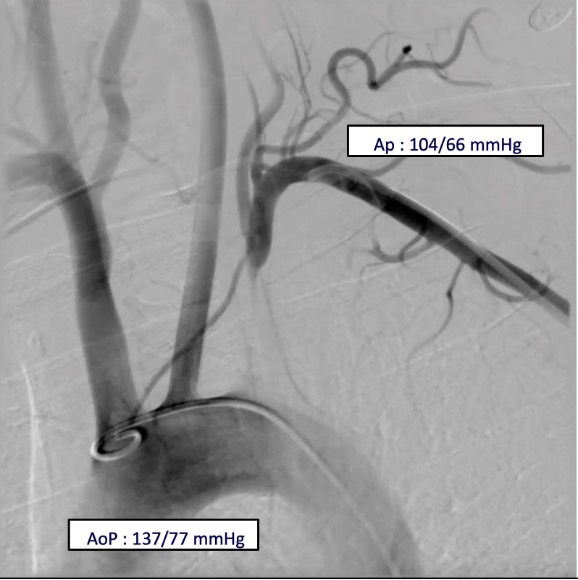

Relevant Catheterization Findings

Vascular access was obtained via ultrasound-guided puncture of the left femoral and radial arteries. A 7 Fr radial GlideSheath and a 6 Fr femoral sheath were inserted. Double contrast injection using 5Fr pigtail in the aortic arch and JR 7Fr in the mid left subclavian atery, demonstrated total occlusion of the proximal left subclavian artery with retrograde flow in the left vertebral artery. The aortic pressure was 137/77 mmHg while the left subclavian artery was 104/66 mmHg.